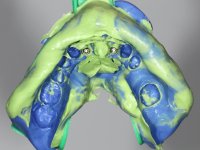

After an imaging study, the placement of two implants of 3.3 mm in diameter and 10 mm in length was planned. On the day of surgery, teeth 42 and 32 were extracted and the implant was removed. The implants were placed in the area of the alveoli, taking care to slightly lingualize their positioning. An impression was made using the open tray technique with the flap open for the fabrication of the immediate provisional bridge. While the impression was taken to the laboratory, tall healing screws were placed and the surgical wound was sutured. The patient waited 2 hours in the waiting room while the temporary bridge was made in the laboratory. An immediate screw-retained provisional bridge was placed and its seating was controlled by imaging. After 3 months, the final impression was made using an open tray technique. In this consultation, we took the opportunity to polish the temporary bridge with rubber cups so that the soft tissues could mature in better conditions. Information was collected to better characterize the monolithic structure in Zr. Color guides were used for the coronal and gingival ceramics. In the laboratory, a bridge was made in Zr. bolt-on that has been carefully characterized. After approval by the patient, it was definitively placed in the mouth. Tightening was performed with a dynamic wrench with a torque of 35 N. The holes were covered with Teflon and filled with composite resin.